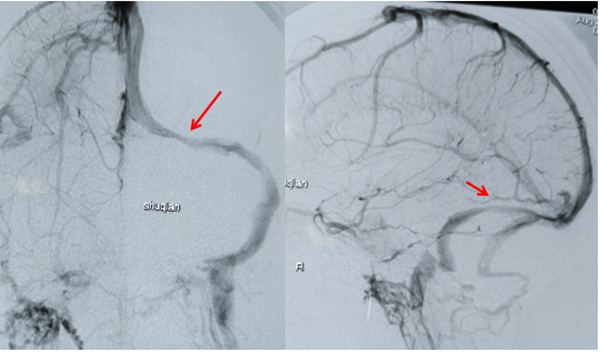

图1 术前造影发现左侧横窦狭窄(箭头处),狭窄两端压力差超过300mmH20

图2 支架植入后狭窄解除(箭头处),血流通畅,两端压力差基本消失